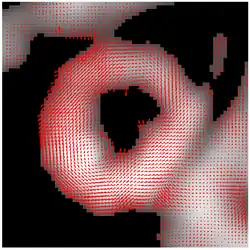

The result of HARP tracking of one frame of cardiac MRI is shown in the figure. It is obtained by calculating both motions from horizontal direction and vertical direction, resulting in a 2D vector field showing the motion of every material point on the myocardium at this time frame.

The entire HARP algorithm takes only a few minutes to perform on a normal computer and the motion tracking result is accurate (with a typical error range of pixel). As a result, it is now widely adopted by the medical image analysis community as a standard processing technique for tagged MRI.